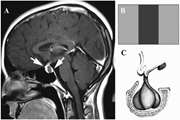

Traumatic atlantoaxial rotatory fixation in adults: a systematic review of published cases 1403/12/26 - 08:34